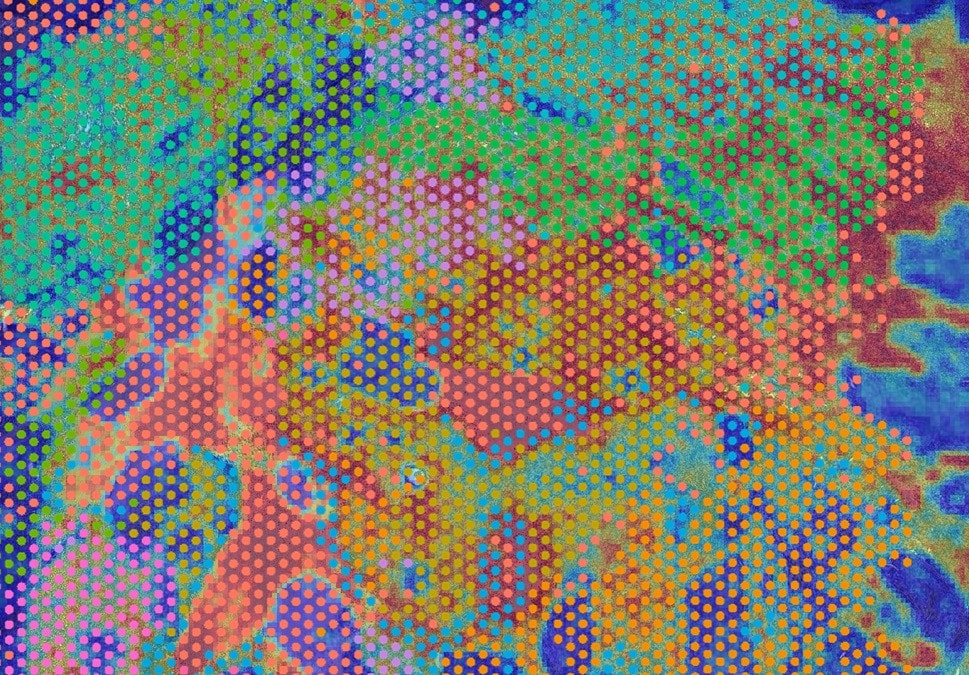

Histologisches Schnittpräparat eines Hirntumors mit herkömmlicher Färbung für die mikroskopische Beurteilung. Die Informationen aus der molekularen Analyse erscheinen als Kreise, die für die Beurteilung relevanten Areale sind rot markiert. (Bild: Universitätsklinikum Heidelberg)